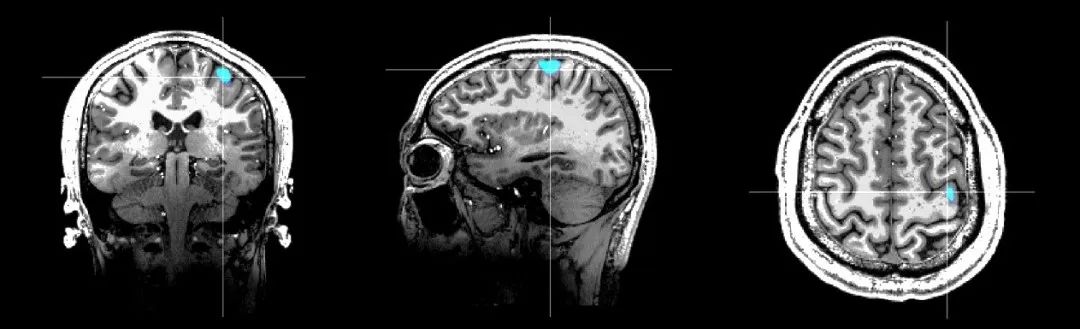

Marvel MEG?ÎÞÒºº¤ÄÔ´ÅͼÒÇÊÇ»ùÓÚÍêÈ«×ÔÖ÷֪ʶ²úȨµÄÐÂÐÍÉúÎKÈõ´Å³¡Ì½²âÊÖÒÕ¡ª¡ªÔ×Ó´ÅÁ¦¼ÆÑз¢¶ø³É£¬£¬£¬£¬£¬¶ÔÄÔ²¿´Å³¡µÄ̽²âѸËٶȵִïÁË10fT¨C 15fT£¨1fT = 10-15Tesla£¬£¬£¬£¬£¬µØÇò´Å³¡µÄÊ®ÒÚ·ÖÖ®Ò»£©¡£¡£¡£¡£¡£¡£Marvel MEG?ÎÞÒºº¤ÄÔ´ÅͼÒÇÒÔ·ÇÇÖÈë·½·¨¼ì²âºÍÏÔʾ´óÄÔÉñ¾×éÖ¯·ÅµçÔ˶¯±¬·¢µÄ´Å³¡Ðźţ¬£¬£¬£¬£¬¾ÙÐÐÄÔ¹¦Ð§³ÉÏñºÍ¾«×¼¶¨Î»¡£¡£¡£¡£¡£¡£¸Ã²úÆ·¼æ±¸ºÁÃë¼¶µÄʱ¼äÇø·ÖÂʺͺÁÃ×¼¶µÄ¿Õ¼äÇø·ÖÂÊ£¬£¬£¬£¬£¬Í¬Ê±ÎÞ´´¡¢ÎÞ·øÉä¡¢ÎÞÐèÔìÓ°¼Á£¬£¬£¬£¬£¬²¢¼¯³É¸ß¾«¶È´Å³¡¿ØÖÆÏµÍ³ºÍ¶àģ̬´Ì¼¤ÏµÍ³£¬£¬£¬£¬£¬¿ÉΪÉñ¾ÏµÍ³¼²²¡µÄ¿ÆÑ§Ñо¿ºÍÁÙ´²Ó¦ÓÃÌṩÎÞ´´¡¢¾«×¼Õï¶ÏµÄÊֶΡ£¡£¡£¡£¡£¡£ÕâÒ»¹ú²ú¸ß¿Æ¼¼×°±¸ÔçǰÒÑ»ñÅú±±¾©ÊÐÁ¢ÒìÒ½ÁÆÆ÷е£¬£¬£¬£¬£¬²¢ÔÚ±±¾©Ìì̳ҽԺ¾ÙÐÐ×¢²áÁÙ´²Ñо¿¡£¡£¡£¡£¡£¡£Í¨¹ý±ÈÕÕÑо¿·¢Ã÷£¬£¬£¬£¬£¬Marvel MEG?ÎÞÒºº¤ÄÔ´ÅͼÒÇʹ³£ÎÂÏÂʵÏÖ³¬¸ßѸËٶȵĴų¡Ì½²â³ÉΪ¿ÉÄÜ£¬£¬£¬£¬£¬¿É½â¾ö¹Å°å³¬µ¼SQUIDÄÔ´ÅͼµÄÍ´µã£¬£¬£¬£¬£¬¾ß±¸³£ÎÂÊÂÇé¡¢ÎÞÐèÒºº¤£¬£¬£¬£¬£¬ÎÞÐ轨Éèµ¥¶ÀµÄ´ÅÆÁÕÏ·¿£¬£¬£¬£¬£¬¼ì²âЧÂÊ¸ßµÈÆæÒìÓÅÊÆ£¬£¬£¬£¬£¬´ó´óÌáÉýÁËÁ¢Òì²úÆ·µÄ¿É¼°ÐÔ¡£¡£¡£¡£¡£¡£

¿µ½¡ÈËÓÒÊÖÔ˶¯¹¦Ð§ÇøÓë7.0TºË´ÅÓ°ÏñÈÚºÏЧ¹û

2022ÄêÓÉδ´Å¿Æ¼¼Ç£Í·µÄ¡°ÐÂÐÍÎÞÒºº¤ÄÔ´ÅͼϵͳÑз¢¡±ÏîÄ¿»ñµÃ¡°Ê®ËÄÎ塱¹ú¼ÒÖØµãÑз¢ÍýÏëÖ§³Ö£¬£¬£¬£¬£¬²¢ÔÚ¿ÎÌâ¼ÓÈ뵥λÊ×¶¼Ò½¿Æ´óѧÁ¥Êô±±¾©Ìì̳ҽԺ¡¢»ªÖпƼ¼´óѧͬ¼ÃҽѧԺÁ¥Êôͬ¼ÃÒ½ÔººÍ±±¾©ÖÐÒ½Ò©´óѧ¶«Ö±ÃÅÒ½Ôº¿ªÕ¹ÁÙ´²ÏàÖúÑо¿£¬£¬£¬£¬£¬¸Ã²úÒ½ÈÚºÏÏîĿȡµÃÁËÒ»´ÎÓÖÒ»´ÎµÄÍ»ÆÆ£¬£¬£¬£¬£¬°üÀ¨¡°È«ÇòÊ×ÀýÎÞÒºº¤ÄÔ´ÅͼÔ˶¯¹¦Ð§Çø¶¨Î»¸¨ÖúϵĽºÖÊÁöÇгýÊÖÊõ¡±¡¢¡°È«ÇòÊ×ÀýÎÞÒºº¤ÄÔ´Åͼ¶¨Î»¸¨Öúϵĺ˴ÅÒõÐÔÄÑÖÎÐÔñ²ðïÊÖÊõ¡±¡£¡£¡£¡£¡£¡£